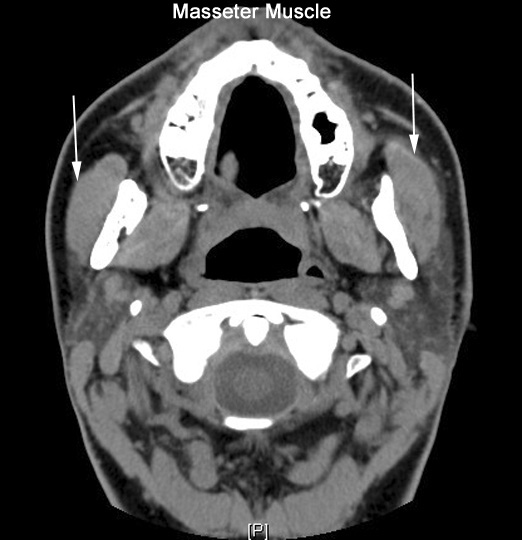

Identify the masseter muscles. Click the image for labeling.